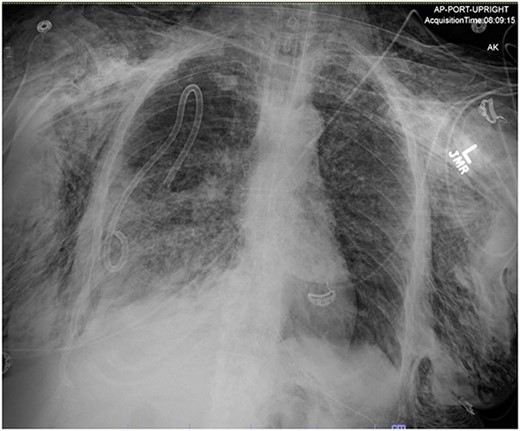

AP upright chest radiograph showing placement of right-sided chest tube and resolution of right pneumothorax.